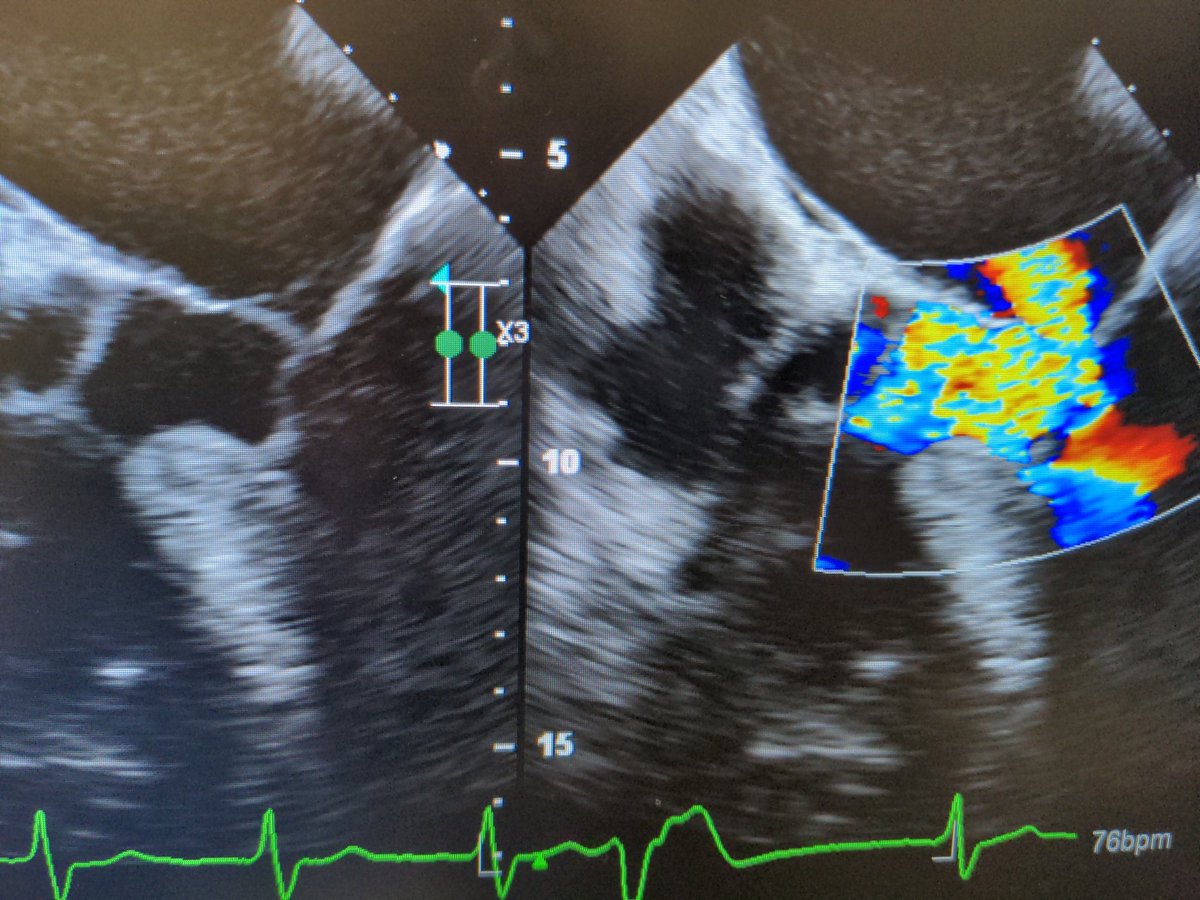

I took a hiatus but am now back! Starting off with this VSD. Heard a loud murmur for a routine pre-op clearance, "no known cardiac history". #echofirst #womenincardiology #Cardiology #CardioTwitter

A good case of LVOTO from SAM of the MV. My first time seeing a case this severe #echofirst #cardiotwitter